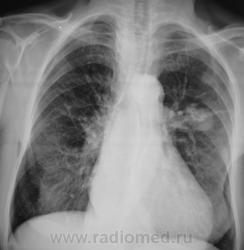

А клиника какова? ПО снимкам можно предположить и новообразование (как мне кажется наиболее вероятно) и туберкулому S6

Помоему образование, тяжистость ну очень интересная.

Неоднородность, очень плотное... гамартрохондрома, тератома, а-v-аневризма... Мне недостаточно для диагностики

Здравствуйте, уважаемый Валентин Львович! Склоняюсь к мысли периферического новообразования. На томограммах хорошо виден патогномоничный симптом "тень на веревочке". Ну и остальное. Неровные, нечеткие контуры, неоднородная структура. Зло!